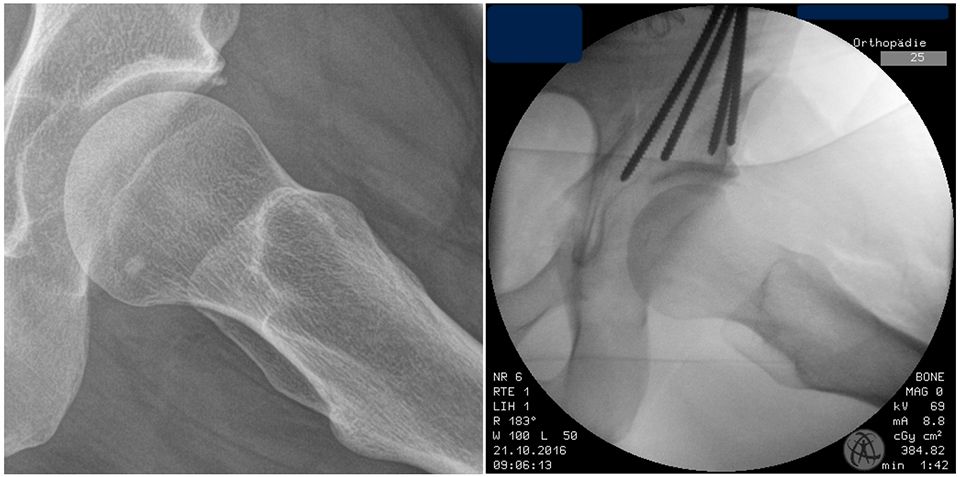

The incomplete ischium osteotomy, preserving the posterior half of the posterior acetabular column, is performed under radiological control with a curved 15mm osteotome. The osteotomy is initiated at the infracotyloid groove, which can be palpated very clearly with the tip of the osteotome, and ascends toward the spina ischadica (Fig. 7). At this point of the operation the surgeon needs to be aware of the anatomical proximity of the sciatic nerve, avoid Intraarticular penetration with the osteotome and guard against transection of the posterior column (Fig. 7, 8). To reduce the risk of nerve injury, the hip is flexed and abducted for the osteotomy of the medial ischium (Fig. 9). For the osteotomy of the lateral ischium the leg is extended and externally rotated.

The retroacetabular osteotomy is performed at an angle of 110° relative to the supraacetabular osteotomy under fluoroscopic control (Fig. 14). Care must be taken to maintain a minimum bone stock of 1 cm prior to the sciatic notch to ensure the integrity of the posterior half of the posterior acetabular column. This ensures the continuity of the posterior column and provides the pelvic stability needed for postoperative mobilization and weight bearing.

After these osteotomies the acetabular fragment should be careful mobilized with a laminar spreader and 1 Steinmann-pin (Fig. 15). Often there are still same bone brides between the ischium and the retroacetabular osteotomies. These bridges should be brocken with a curved osteotome which is placed under fluoroscopic control and after spreading the osteotomy with a laminar spreader. After all osteotomies are finished, acetabular reorientation remains a difficult step and care should be taken to achieve proper acetabular reorientation. The goal of reorientation is an LCE of 30°, a positive acetabular index and an anteverted acetabulum The reoriented acetabulum is then temporarily secured by two Kirschner wires that bridge the supraacetabular osteotomy (Fig. 15).

To avoid postoperative limitation in ROM or femoroacetabular impingement the freedom of motion after reorientation and before definite fixation of the acetabular fragment should be checked with minimum of 120° flexion and 30° internal rotation in 90° hip flexion. If an optimal acetabular reorientation and adequate ROM has been achieved the acetabular fragment is definitely fixed with four 4,5mm screws. The screw placement is verified with fluoroscopy to verify their extraarticular position (Fig. 16).